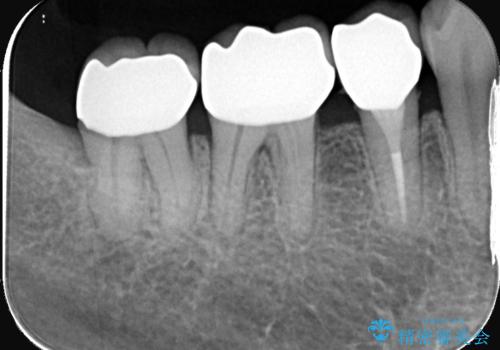

- 「銀歯が目立つのがずっと気になっていた」とのご相談で来院されました。左下の奥歯(5・6・7番)には保険治療で入れた銀色の被せ物が入っており、笑ったときや口を開けた際に見えるのが気になるとのことでした。

歯ぐきの状態やかみ合わせを確認したところ、被せ物の適合に大きな問題はなかったものの、審美的な観点から、白く自然な見た目のセラミッククラウンにやりかえることで、より快適に過ごしていただけると判断しました。セラミックは金属を使わないため、見た目が自然で、金属アレルギーの心配もない素材です。長期的な予後の安定も見込めるため、審美と機能を両立した治療計画をご提案しました。

まずは銀歯を慎重に取り外し、歯の状態を確認しました。虫歯や劣化した部分は丁寧に除去し、必要に応じて土台を整えたうえで、セラミッククラウンを作製する準備を行いました。色や形は周囲の歯になじむように細かく調整し、自然な透明感やツヤを再現しました。

最終的には、左下5・6・7番の3本すべてをセラミッククラウンに置き換え。白くなったことで口元の印象が明るくなり、見た目だけでなく、かみ合わせも良好に仕上がりました。